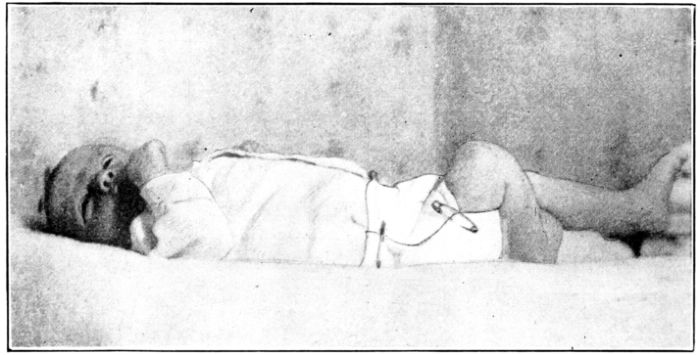

| 180. | Baby wrapped in blanket preparatory to gavage | 523 |